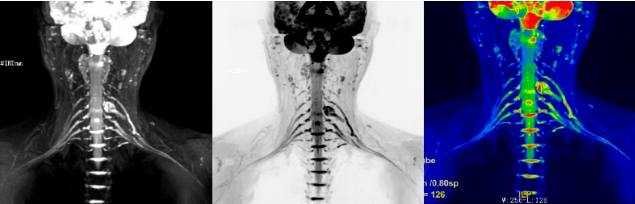

术后复查

目前此项检查应用于:臂丛神经节前及节后损伤、臂丛神经损伤分型、臂丛神经源性肿瘤、急性臂丛神经炎、臂丛神经放射性纤维化、肿瘤侵犯臂丛神经、胸廓出口综合征、四边孔综合征等。